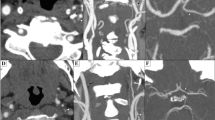

A 75-year-old woman underwent left internal carotid artery ligation and placement of a radial arterial graft. a–e Three-dimensional surface-rendered arterial images of time-resolved 3D phase contrast (4D flow) MRI generated by GT Flow software. Each of the five images provides the flow at each time point. The two regions of interest (ROIs) for flow analysis were in a grafted artery (arrows, a) and at the right internal carotid artery (ICA) (arrowheads, a). The red pathline, which simulates blood flow from the ROI of the bypass artery, runs through the bypass artery (arrows, b), the left M1 (arrows, c), and the left A1 (arrows, d). Part of this flow runs through the right A1 together with the blue pathline (arrows, e), which simulates blood flow from the right ICA. The images clearly depict patency of the bypass, retrograde flow of the ipsilateral M1, and antegrade flow of the ipsilateral A1. The ipsilateral postcommunicating artery is unclear. Graft flow was 3.97 ml/s, right ICA flow 9.69 ml/s, and basilar artery flow 4.14 ml/s. For a more detailed description, the reader is referred to Supplementary Movie 1

The flow volume in the BA was not calculated in two patients because it was out of the FOV. There were no apparent artifacts (e.g., motion artifact, susceptibility artifact by implant) that caused MRI deterioration. Representative cases are given in Fig. 2 and Supplementary Movie 1. EC-IC bypass flow was successfully generated in all patients. Nonnative, retrograde flow was observed at the M1 segment of the MCA in 10 of the 19 patients. Retrograde flow at M1 was observed more frequently in patients with a RAG bypass than in those with an STA bypass (p < 0.01) (Table 1). The BFVs of the bypass arteries were significantly higher in patients with a RAG bypass than in those with an STA bypass (3.19 ± 1.13 vs. 1.68 ± 0.97 ml, p < 0.01). In contrast, there was no correlation of the BFV of the contralateral ICA or BA with the type of bypass artery (Table 2). The BFV in the bypass artery significantly (but only slightly) correlated with the arterial diameter of the CTA (p < 0.05, R 2 0.287) and not with that of the TOF-MRA (Fig. 3). One Pcom was hypoplastic on CTA and TOF-MRA. Other arteries were detectable on both CTA and TOF-MRA. In these 29 arteries, the detectability of flow direction in the ipsilateral A1 segment and the Pcom artery were significantly correlated with the arterial diameter seen on TOF-MRA (p < 0.01) but not with that of the CTA (Fig. 4). The cutoff values for the CTA and the TOF-MRA arterial diameters to detect the artery on 4D flow MRI were 2.4 and 1.8 mm, respectively.

There were four major findings in this study: (1) the patency of the bypass and the flow direction in the M1 segment of the MCA in patients with EC-IC bypass were successfully generated by 4D flow MRI; (2) the flow characteristics after bypass surgery differed depending on the presurgerical condition and the choice of bypass artery; (3) the flow volume of the bypass artery had a weak correlation with the arterial diameter on CTA and no correlation on MRA; and (4) the detectability of flow directions in small arteries on 4D flow MRI had a significant but slight correlation with the arterial diameter on MRA, and detectability was not correlated with arterial diameters on CTA.

This study revealed that flow patterns and BFVs differed between the RAG and STA groups because of differences in the diameters and the role of the bypass. The RAG bypass vessel has a wider diameter and plays a role in flow replacement, whereas the STA bypass has a narrow diameter, which plays a role in flow augmentation [3]. In this study, 4D flow MRI provided comprehensive and objective evaluation of this difference. Bypass function has traditionally been assessed by a grading system using angiographic images [14], with the vascular tree filled with contrast material injected from the bypass artery. However, such a grading system is difficult to quantify and less easy to reproduce. Also, manual injection of a contrast medium causes nonphysiologic hemodynamics. Although this effect may be small, 4D flow MRI offers more accurate imaging. Some state-of-art MRI techniques have been performed to assess hemodynamics in patients with EC-IC bypass [10, 12, 16]. However, it is difficult to provide initiative results or information on each vessel (i.e., which vessels are perfused by blood flowing through from the bypass).